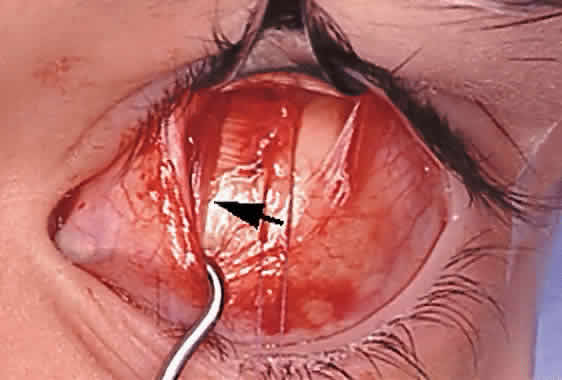

The superior oblique tendon tuck is best performed near the tendon's insertion as described by McLean.48 The surgical procedure is performed through a superior temporal cul-de-sac approach (Fig. 4). With the globe depressed, an incision is made through the conjunctiva and Tenon's fascia just temporal to the lateral border of the superior rectus muscle and parallel to the corneoscleral limbus. The superior rectus muscle is engaged on a muscle hook and the globe adducted and positioned in maximal depression. The lateral rectus muscle may also be used to assist positioning the globe. Using two small muscle hooks, the conjunctival incision is stretched open posteriorly in a triangular fashion. The lateral border of the superior rectus muscle is elevated and displaced medially. The globe is then examined for the glistening, white fibers of the superior oblique tendon running flush against the sclera and directed anteromedially. The anterior portion of the reflected tendon typically inserts under the lateral border of the superior rectus muscle, 5 to 7 mm posterior to its insertion. However, this location may vary, and anatomic anomalies are common (Fig. 5).12,37,47,48 The superior oblique tendon looks very different near its scleral insertion than 10 mm more proximally, where it becomes cordlike and enters Tenon's fascia after passing under the belly of the superior rectus muscle. Inexperienced surgeons have mistaken the lateral portion of the tendinous insertion of the superior rectus muscle for the superior oblique tendon (Fig. 6).49 However, the superior rectus muscle travels toward the orbital apex and contains prominent anterior ciliary blood vessels, whereas the superior oblique tendon is directed toward the trochlea and is usually avascular. In addition, direct traction on the superior oblique tendon can easily be palpated at the trochlea by pressing a finger over the eyelid in the superior nasal quadrant of the orbit.10 This is a reliable sign that the tendon (and not some other structure) has been engaged on the muscle hook.

Serious complications of superior oblique muscle strengthening are infrequent. Intraoperative complications relate primarily to orbital hemorrhage from injury to a vortex vein or unintended entry into the orbital fat space, which results in an adherence syndrome with restricted ductions postoperatively. These can be avoided by good surgical exposure, use of loupe magnification with a surgical headlight, and deliberate and meticulous surgical technique. The superior oblique tendon can be surgically missed or inadvertently cut during dissection of the intermuscular septum. Anatomic variations including absence of the tendon are common.12 Confusion can also occur if the surgeon inadvertently engages the superior oblique tendon when first attempting to hook the superior rectus muscle.49 However, this is less common when the superior oblique tendon is approached temporally rather than nasally (Fig. 9). Surgical overcorrection occurs frequently, but it is fortunately not permanent in most patients. However, permanent overcorrection that results in a primary gaze position hypotropia is usually an unacceptable result and requires reoperation. It can be caused by excessive surgical dosage, spontaneous recovery of superior oblique muscle function, or failure to recognize bilateral superior oblique muscle palsy preoperatively.

Iatrogenic Brown's syndrome is an unavoidable complication of superior oblique muscle strengthening and occurs in almost 100% of patients undergoing superior oblique tendon tuck. It is virtually identical in clinical appearance to congenital Brown's syndrome, which is discussed later in this chapter (Fig. 10). In the absence of excessive tendon shortening, the limitation of elevation in adduction almost always improves with time and reoperation for this entity is rarely required. Tendon tucking medially (rather than temporally) to the superior rectus muscle is more hazardous because of proximity to the trochlea. Patients with persisting overcorrection in primary gaze position and at least moderate Brown's syndrome (no elevation above the horizontal meridian in adduction) are usually symptomatic and should have their tucks removed. However, adhesions between the superior rectus muscle, superior oblique tendon, and the globe are likely to be present and must be freed to normalize ductions. In general, tuck take down should be performed without simultaneous surgery on other cyclovertical muscles.